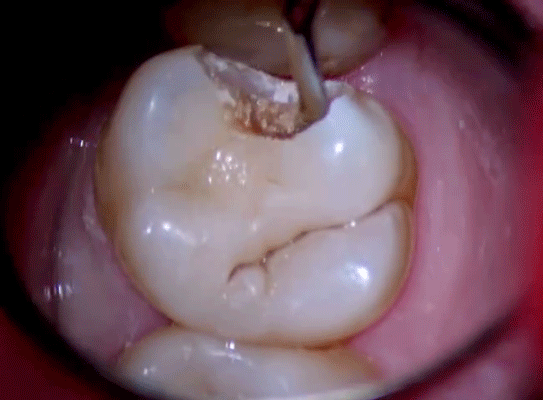

补一次牙,少则几百多则上万,自己疼得受罪,补过的牙也没原来的好使.

牙齿烂了,补牙还是拔牙?